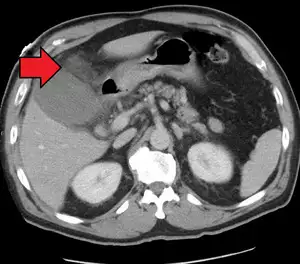

AcuteCholMark.png

Acute cholecystitis as seen on CT. Note the fat stranding around the enlarged gallbladder.